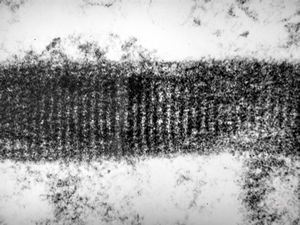

F,44y. | striations of fibrin - heart atrium, myxoma

M,28y. | striations of fibrin - aortal valve, endocarditis

F,39y. | collagen and elastin - aorta

F,39y. | collagen, elastin and oxytalan microfibrils

F,45y. | collagen fibril - skin

F,29y. | collagen, elastin and oxytalan microfibrils - endomyocardial fibrosis